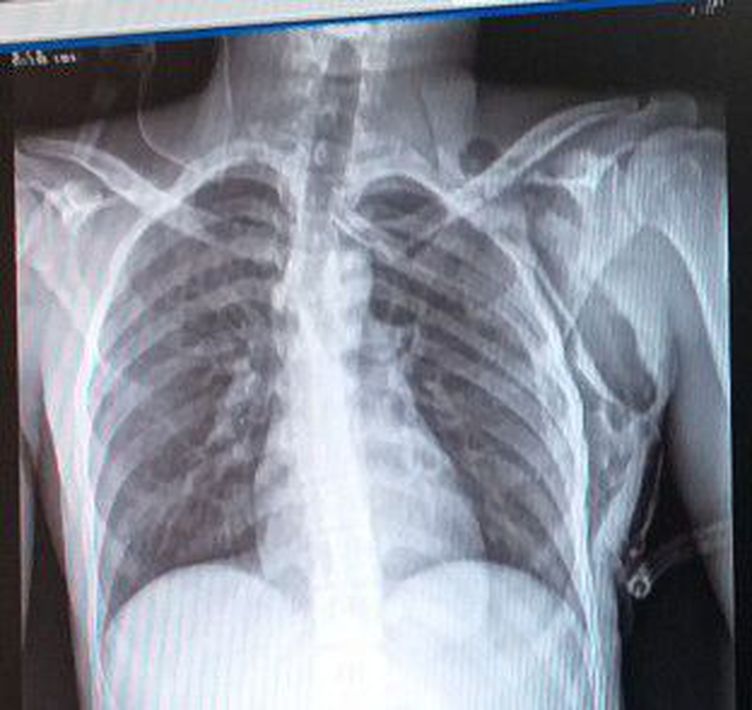

What is your diagnosis?

Subcutaneous emphysema